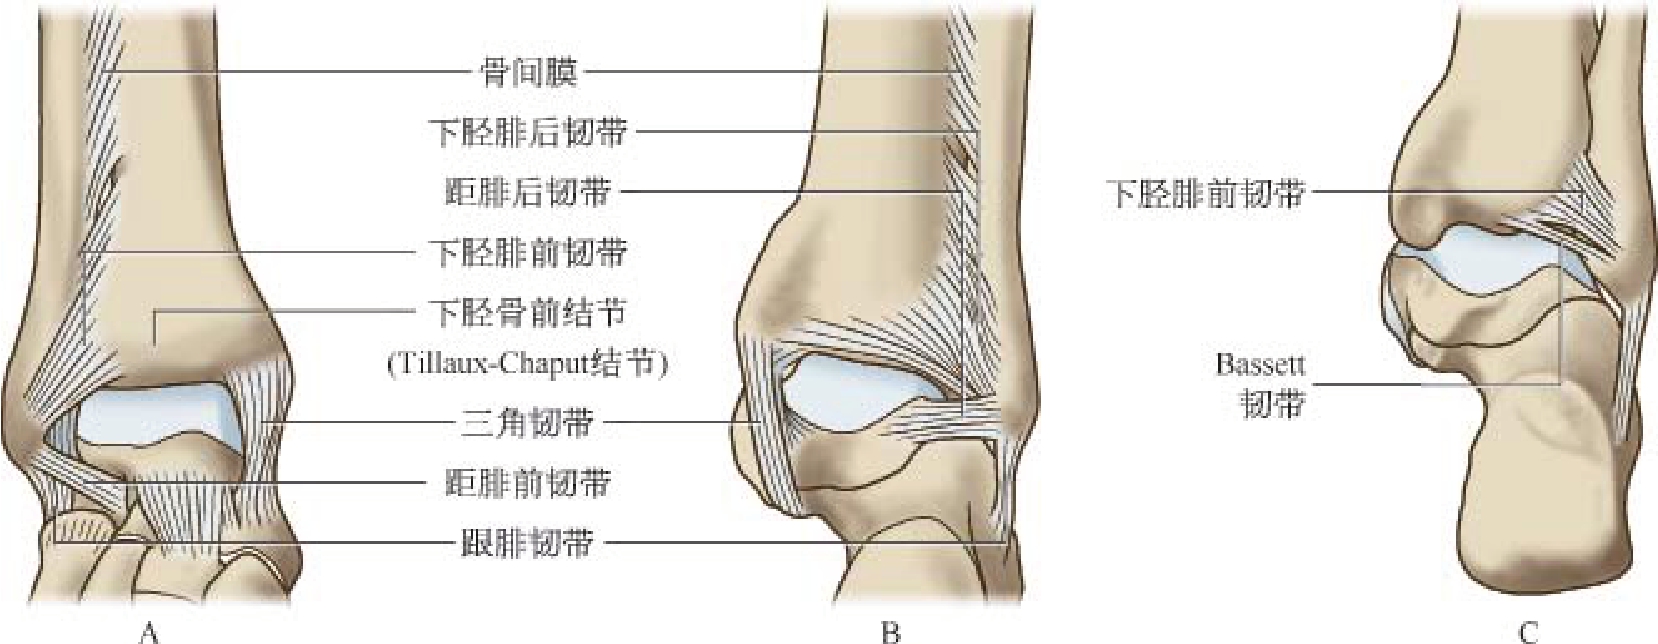

1.18.1.1(一)下胫腓韧带复合体

1.18.1.2(二)侧副韧带复合体